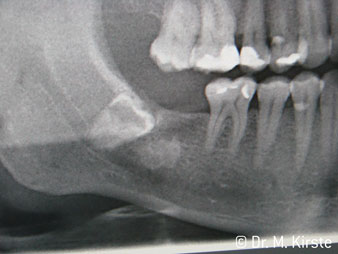

45° açılı angldruva geniş avantaj yelpazesi sebebiyle özellikle seçildi. Bu enstrümanın geliştirilme nedeni olan cerrah meslektaşlarım angldruvaların kısıtlı alanlardaki çalışma yeteneğini yakında takdir edeceklerdir. Özellikle gömük diş çekimlerinde (res. 2) yumuşak dokunun yanak bölgesine doğru yarılmasına gerek kalmaz(res. 3). Angldruvanın kafa dizaynı sayesinde retromolar bölgede hızlı ve güvenli çalışma sağlar.

Angldruva kafası içindeki profesyonel tasarımlı dişliler frezin sessiz çalışmasını garanti eder; kök separasyonu yapılırken atravmatik operasyona olanak verir. (res. 4-9).